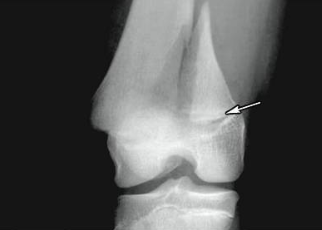

epiphyseal fracture